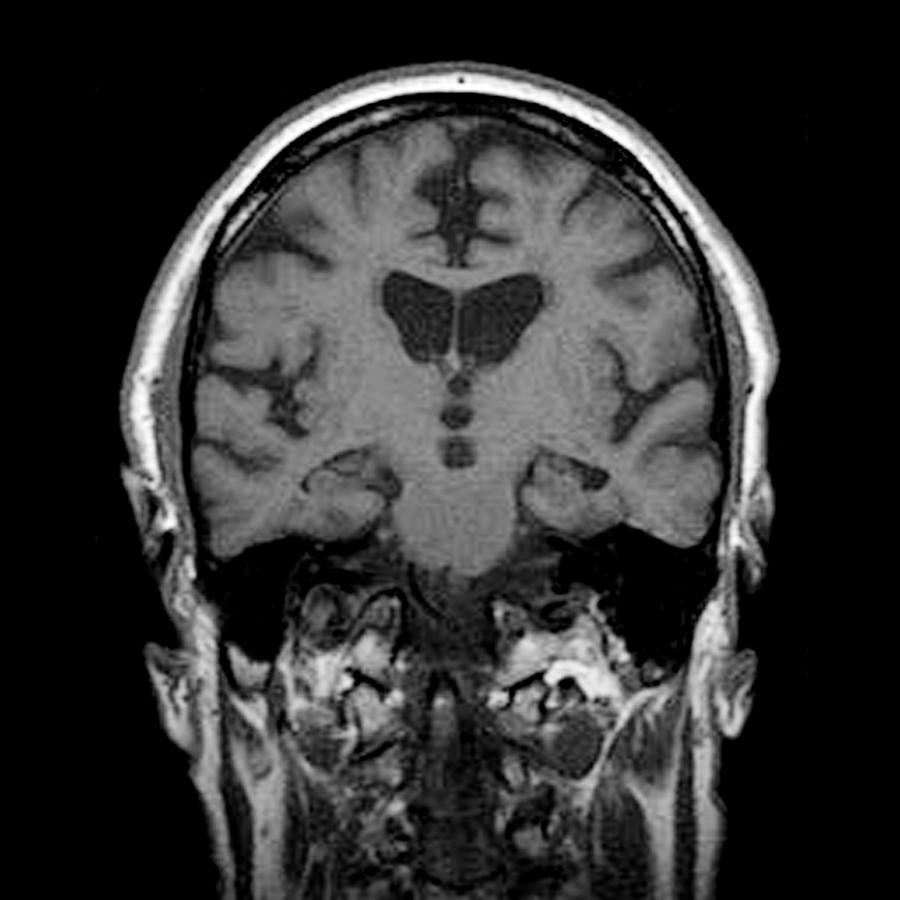

images of dementia brain

What Does The Brain Look Like With Dementia – DementiaTalkClub.com

Can Ct Scan Detect Alzheimers – Dementia Talk Club

Alcoholic Dementia, Mri Scan Photograph by Du Cane Medical Imaging Ltd

Alcoholic Dementia, Mri Scan Photograph by Du Cane Medical Imaging Ltd

Alcoholic Dementia, Mri Scan Photograph by Du Cane Medical Imaging Ltd

Dementia, MRI scans – Stock Image – M140/0433 – Science Photo Library

Using MRI scans to reveal early signs of dementia | Health-RI

Dementia brain ct hi-res stock photography and images – Alamy

Dementia brain ct hi-res stock photography and images – Alamy

Dementia brain scan hi-res stock photography and images – Alamy

Dementia Brain Stock Photos & Dementia Brain Stock Images – Alamy